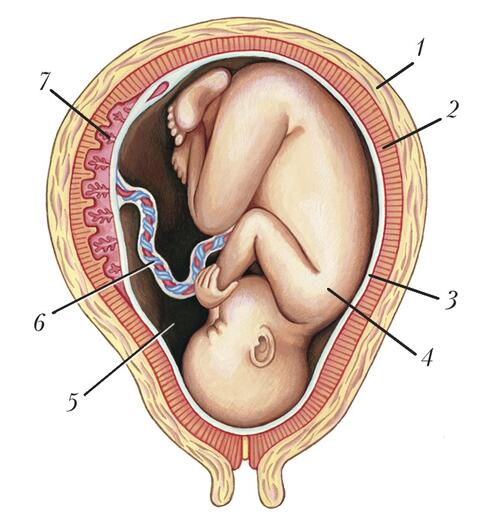

Околоплодный пузырь и плацента: структура и функции